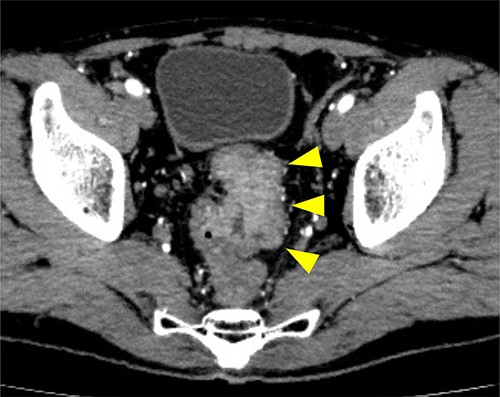

A 53-year-old Japanese man was admitted to the hospital with a chief complaint of buttock pain that lasted for 5 months and a recent weight loss of 8 kg, from 68 kg to 60 kg. He had no remarkable medical history. Digital rectal examination could not be performed because of severe pain. Laboratory findings revealed severe inflammation, indicated by an increased white blood cell count (16 790 cells/μL) and C-reactive protein (12.15 mg/dL). He was also undernourished with an albumin level of 2.7 g/dL. Tumor marker levels of carcinoembryonic antigen and cancer antigen 19–9 were within the normal ranges. Pelvic computed tomography (CT) showed contrast-enhanced thickening of the upper rectal wall and perirectal abscess (Fig. 1). Swollen lymph nodes were observed near the mesentery, but distant metastases were not detected. Rectal cancer accompanied by a pelvic abscess was then suspected. For the patient’s relief, sigmoid colonoscopy was performed under lumbar spinal anesthesia, which revealed a semicircular type 2 tumor in the upper rectum (Fig. 2a), and exclusion from outside the rectal wall on the anal side of the tumor at 7 cm from the anal verge (Fig. 2b). The colonoscope could not pass through the oral side of the tumor.

Contrast medium-enhanced CT upon admission in axial (a) and sagittal (b) sections. Irregular thickening of the rectal wall (arrowheads) and an accompanying pelvic abscess (arrows) are observed. No evident distant metastases are observed.